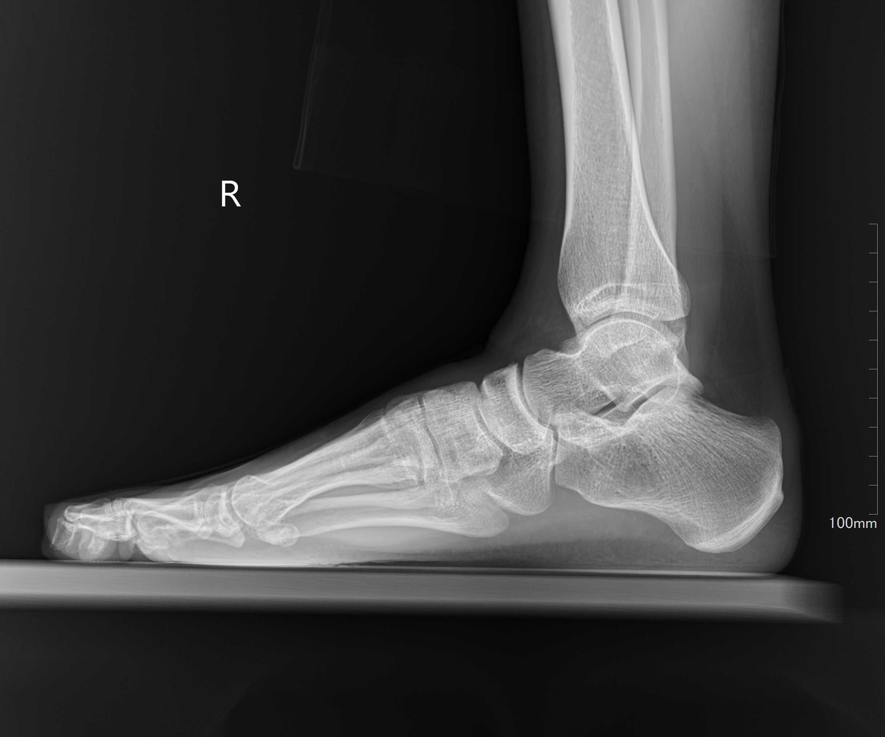

受診時、まずレントゲン検査を実施しましたが、骨に異常は認められませんでした。